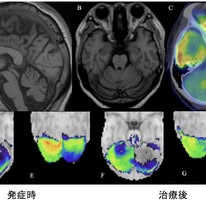

症例は55歳女性で,ゴリムマブ導入1か月後に歩行時のふらつきと構音障害が出現し,約8か月で進行しました.神経学的には断綴性構音障害,右優位の四肢の運動失調,失調性歩行を認めました.脳脊髄液検査では,細胞数は正常で,IL-6やTNF-αも正常範囲でしたが,IgG indexが1.44と上昇しており,中枢神経内での免疫活性化が示唆されました.オリゴクローナルバンドは陰性.画像所見では,MRIで軽度の小脳萎縮を認めました(図1上左).FDG-PETでは両側小脳の集積低下(図1上右),SPECTでは右優位の両側小脳低灌流が認められました(図1下;decrease画像で,色が赤くなるほど血流低下を示します).

Tissue-based assayでは患者脳脊髄液IgGが小脳分子層ニューロピルに結合し,培養海馬ニューロンの細胞表面にも反応することが示され,細胞表面抗原に対する抗神経抗体の存在が強く示唆されました(図2).一方でmGluR1抗体やGAD抗体などの既知の抗体は陰性であり,標的抗原は同定できていません.

治療としてゴリムマブ中止とステロイドパルス療法を行い,小脳性運動失調は改善し,SARAスコアは9から5へ低下しました.SPECTでの低灌流所見およびIgG indexも改善し,免疫異常と臨床症状が並行して可逆的に改善した点は,本病態が自己免疫機序によることを支持します.